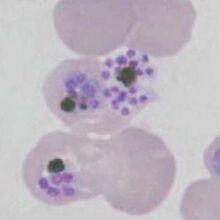

The schizont

The schizont is the asexual form of the malaria parasite that will circulate in blood in most species, but is an uncommon feature in P.falciparum:

- Do not generally circulate in this species consider causes

- The merozoites cluster "untidily" but may be numerous (8-16+ when mature)

- In this species the loose pigment may be seen in clumps between the parasites

- Red cell size is generally unaffected but red cells become pale as haemoglobin is metabolised by the parasites

P.falciparum schizonts